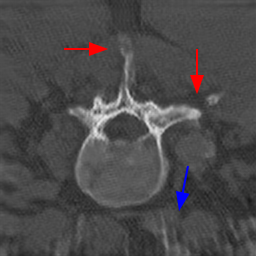

Disentanglement and explicit shape constraints. As shown in Fig. 4, we can see streak metal artifacts nearly everywhere in . M1 can roughly disentangle artifacts and anatomical information but strong vertical artifacts and strange air area appear in (see red arrows of M1 in Fig. 4). For the anatomical structure, M1 learns to segment vertebrae with fully supervised and applied on various CT images, but fails to suppress the false bony structure in and as may misclassify some metal artifacts as bone.

Implicit shape constraints. With , all segmentations are improved with higher Dices and smaller ASDs, see Table 1. As shown in Fig. 4, , and become similar but the high density bone is not correctly segmented in as it maybe treated as metal artifacts. Comparing between M2 and M1, the abnormal air region disappears but metal artifact reduction performance is still not satisfactory.

Anatomy-aware generation. With AADE layer in M3, , and are substantially improved as shown in Table 1. Note, is used as attention map, so we do not expect it to be identical to . In , metal artifacts are further suppressed comparing with M2. Thus, AADE is critical to our anatomy-aware artifact disentanglement framework. With the special structure, can be punished in the image translation and reconstruction processes and the other encoders and generators receive more guidance. However, as shown by blue arrows in Fig. 4, we observe a shadow of vertebra edge of appears in of M3 and the vertebra boundaries get smoothed out in . It may be because sharp edges are encoded as metal artifacts and forced to be added to by artifact consistency loss .

Removal of . To mitigate vertebrae shadows, we remove . The segmentation performance of most images in M4 gets improved because of better synthetic images. Overall, in M4 yields the best segmentation performance for CBCT images with an average Dice of 0.847 and an average ASD of 1.54 mm. For the synthetic images, M4 generates with the best quality and least metal artifacts among all the models. M4 also outputs without vertebra shadows. The results indicate our shape-aware network could preserve anatomical details and transfer the metal artifacts precisely without .